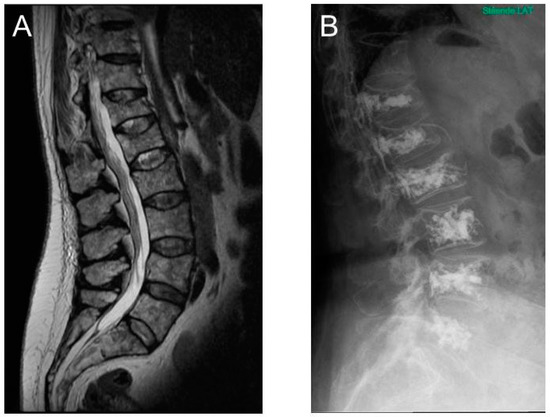

3.3. MRI as a Diagnostic and Prognostic Tool in Patients with Multiple Myeloma

5.2. Vertebral Augmentation

- Mauch, J.T.; Carr, C.M.; Cloft, H.; Diehn, F.E. Review of the Imaging Features of Benign Osteoporotic and Malignant Vertebral Compression Fractures. Am. J. Neuroradiol. 2018, 39, 1584–1592. [Google Scholar] [CrossRef]

- Berenson, J.; Pflugmacher, R.; Jarzem, P.; Zonder, J.; Schechtman, K.; Tillman, J.B.; Bastian, L.; Ashraf, T.; Vrionis, F. Balloon kyphoplasty versus non-surgical fracture management for treatment of painful vertebral body compression fractures in patients with cancer: A multicentre, randomised controlled trial. Lancet Oncol. 2011, 12, 225–235. [Google Scholar] [CrossRef]

- Julka, A.; Tolhurst, S.; Srinivasan, R.; Graziano, G. Functional Outcomes and Height Restoration for Patients with Multiple Myeloma-Related Osteolytic Vertebral Compression Fractures Treated with Kyphoplasty. J. Spinal Disord. Tech. 2014, 27, 342–346. [Google Scholar] [CrossRef]

- Simony, A.; Hansen, E.J.; Gaurilcikas, M.; Abildgaard, N.; Andersen, M.O. Pain reduction after percutaneous vertebroplasty for myeloma-associated vertebral fractures. Dan. Med. J. 2014, 61, A4945. [Google Scholar]